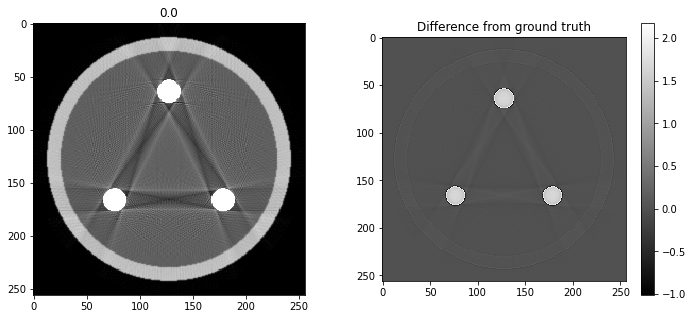

# Question 12

search = np.linspace(0,1,11)

for alpha in search:

rec = out+alpha*reproj

f,ax = plt.subplots(1,2,figsize=(12,5))

ax[0].imshow(rec,vmin=0,vmax=0.5)

ax[0].set_title(alpha)

im = ax[1].imshow(img[80]-rec)

f.colorbar(im,ax=ax[1])

ax[1].set_title('Difference from ground truth')

plt.show()